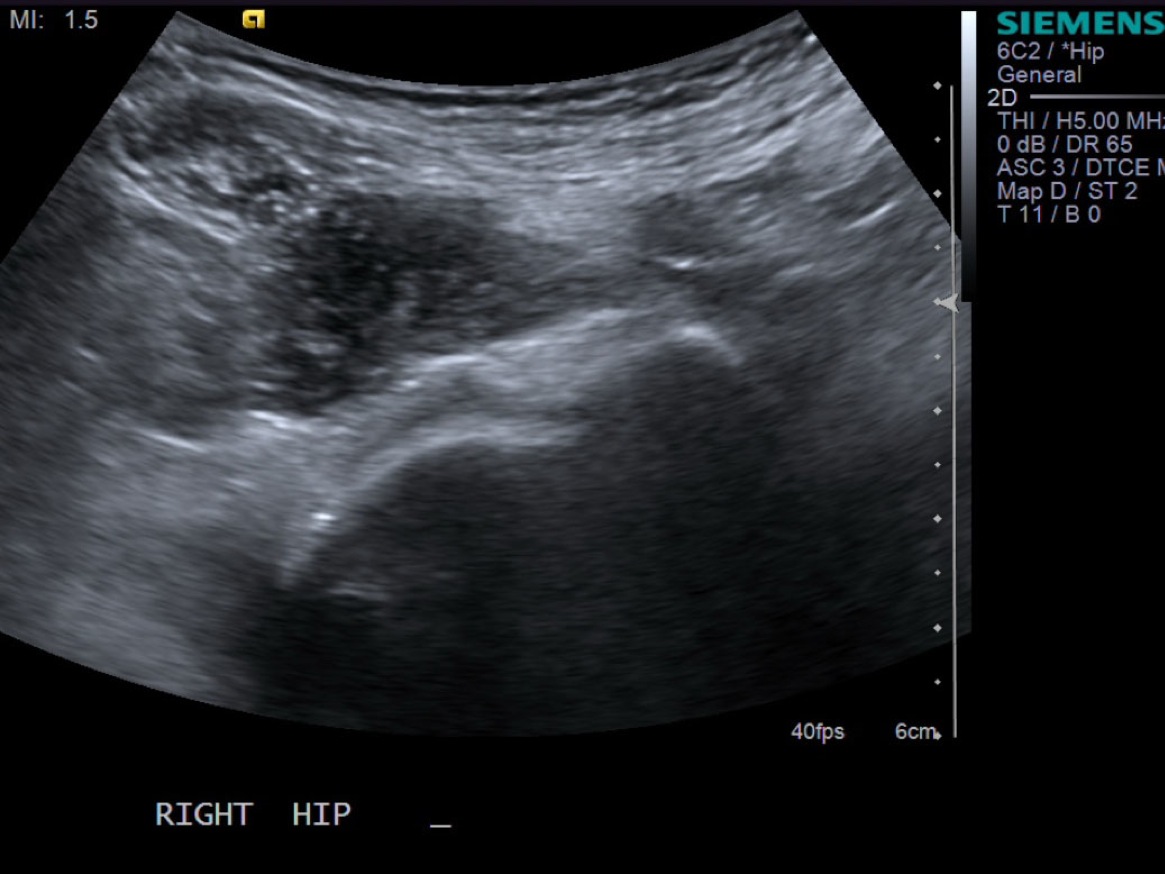

2.Position patient supine.

• descriptiondescription

Transverse/short axis view of iliopsoas tendon